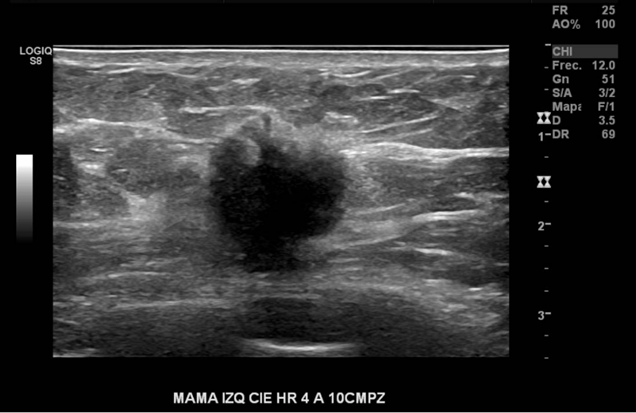

Nódulo sólido, de bordes irregulares, con sombra acústica posterior, gran tamaño, no palpable en CIE HR 4 a 10 cm pz en mama izquierda. Por su ubicación, no es visible en Mx

En el cuadrante inferior externo de la mama izquierda a la hora 4 a 10 cmp, se observa un nódulo hipoecogénico, ovalado, de bordes irregulares con microcalcificaciones en su interior, escasamente vascularizado y bien definido, de 20 mm de diámetro.

Nódulo mamario izquierdo altamente sugerente de malignidad.

BIRADS US 5

Se sugiere correlación histológica.